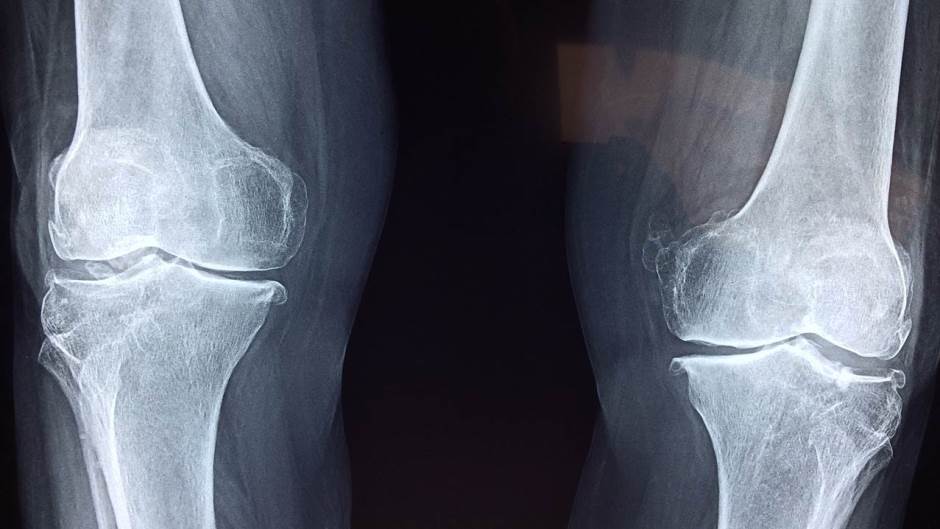

Ugradnja endoproteze kuka i koljena dvije su najučestalije operacije u ortopedskoj kirurgiji, ali liječnicima je uvijek teško kada trebaju odgovoriti pacijentu koliko će im trajati implantati.

Endoproteza kuka: 89 posto umjetnih zglobova trajalo je 15 godina; 70 posto 20 godina; 58 posto 25 godina

Potpuna endoproteza koljena: 93 posto trajalo je 15; 90 posto 20 i 82 posto 25 godina.

Djelomična endoproteza koljena: 77 posto trajalo je 15; 72 posto 20 i 70 posto 25 godina.

Teškoće koje se pojavljuju s umjetnim zglobovima kuka i koljena uglavnom su povezane s infekcijom i habanjem, ali rjeđe s lomom. U tom slučaju pacijentima je potrebna reugradnja, a tada su rizici za neuspjeh veći.